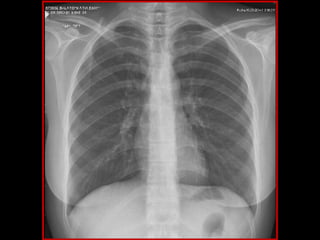

Examen neurológico: Fuerza ysensibilidad en cuatro miembros conservada Hiperreflexia patelar y aquilea con clonus inagotable en MMII Marcha espástica Pares craneales y MMSS sin hallazgos patológicos